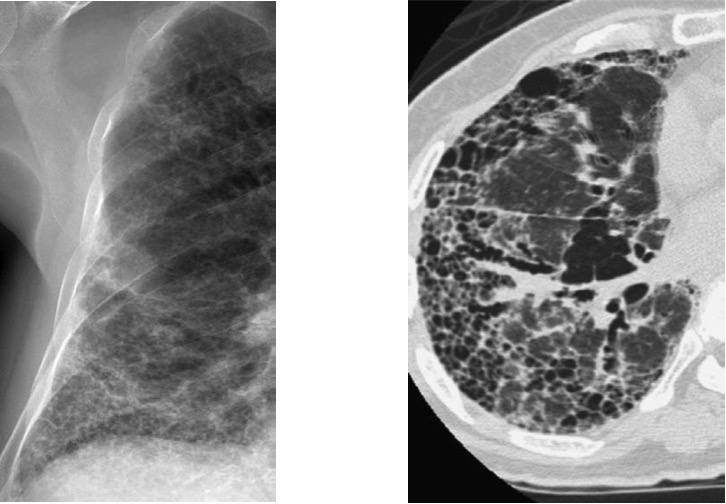

– Caso. Patrón en panal: Opacidades pulmonares subpleurales con imágenes aéreas quísticas menores de 1cm en su interior con un aspecto reticular. Suele acompañarse de pérdida de volumen por patología restictiva. La presencia de panalización puede significar lesión destructiva final con fibrosis y distorsión de la arquitectura pulmonar de grado severo.

Causas:

- Enfermedades del Tejido conectivo (esclerodermia, artritis reumatoide, dematopolimiositis, polimiositis).

- Fibrosis pulomnar idiopática, Neumonía intersticial usual.

- Histiocitosis X.

- Neumoconiosis.

- Sarcoidosis.